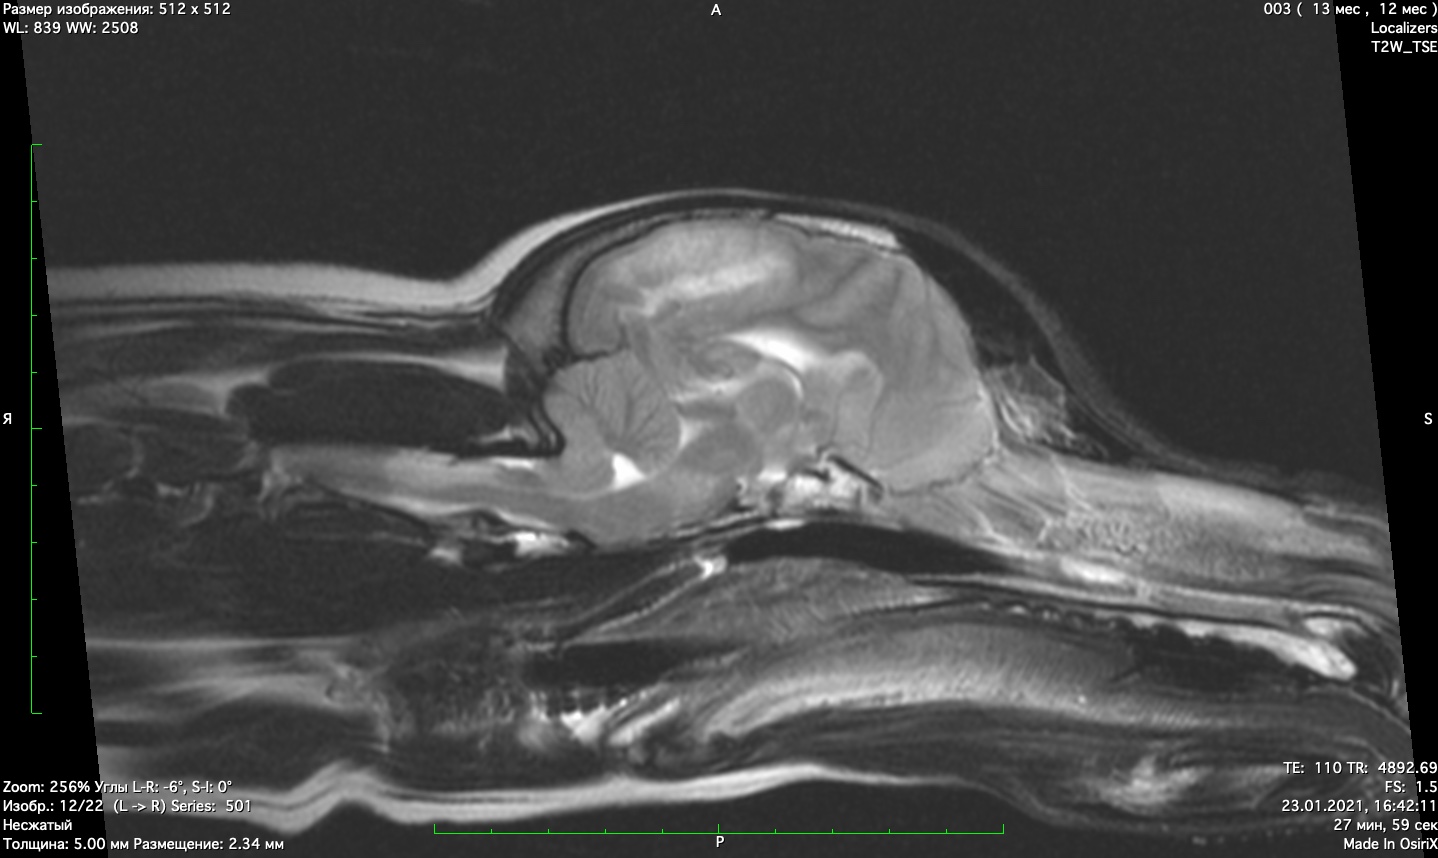

При проведении мрт диагностики установлено признаки мультифокального поражения головного мозга поставлен диагноз гранулематозный менингоэнцефалит неизвестной этиологии. Начато иммуносупрессивное лечение